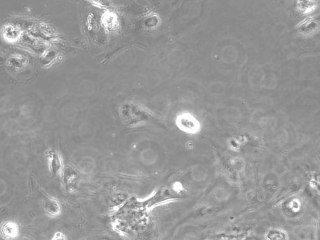

Glioma Cell Death